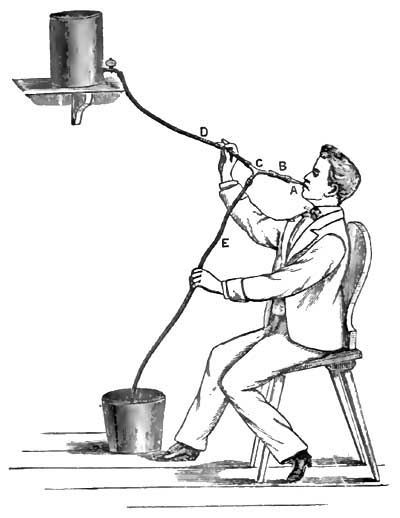

| 22. | ROSENTHAL'S METHOD OF WASHING OUT THE STOMACH |

| 23. | ANTERIOR VIEW OF A STRANGLUATED INTESTINE AND STRICTURE |